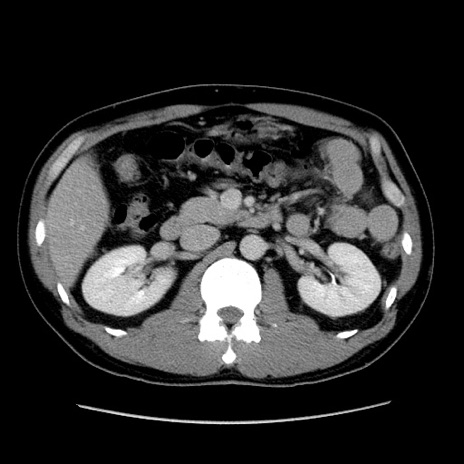

症例4(横断像)

【症例】30歳代男性

【主訴】腹痛、嘔吐

【現病歴】昨晩から突然の腹痛あり、その後嘔吐、軟便も出現。腹痛が改善しないため救急搬送となる。2日前にしめ鯖の食事歴あり。

【身体所見】意識清明、苦悶様、BP 135/90mmHg、BT 35.7℃、腹部:平坦、やや硬、心窩部〜臍部に自発痛、圧痛あり、筋性防御+、反跳痛-

【データ】WBC 8100、CRP 0.57